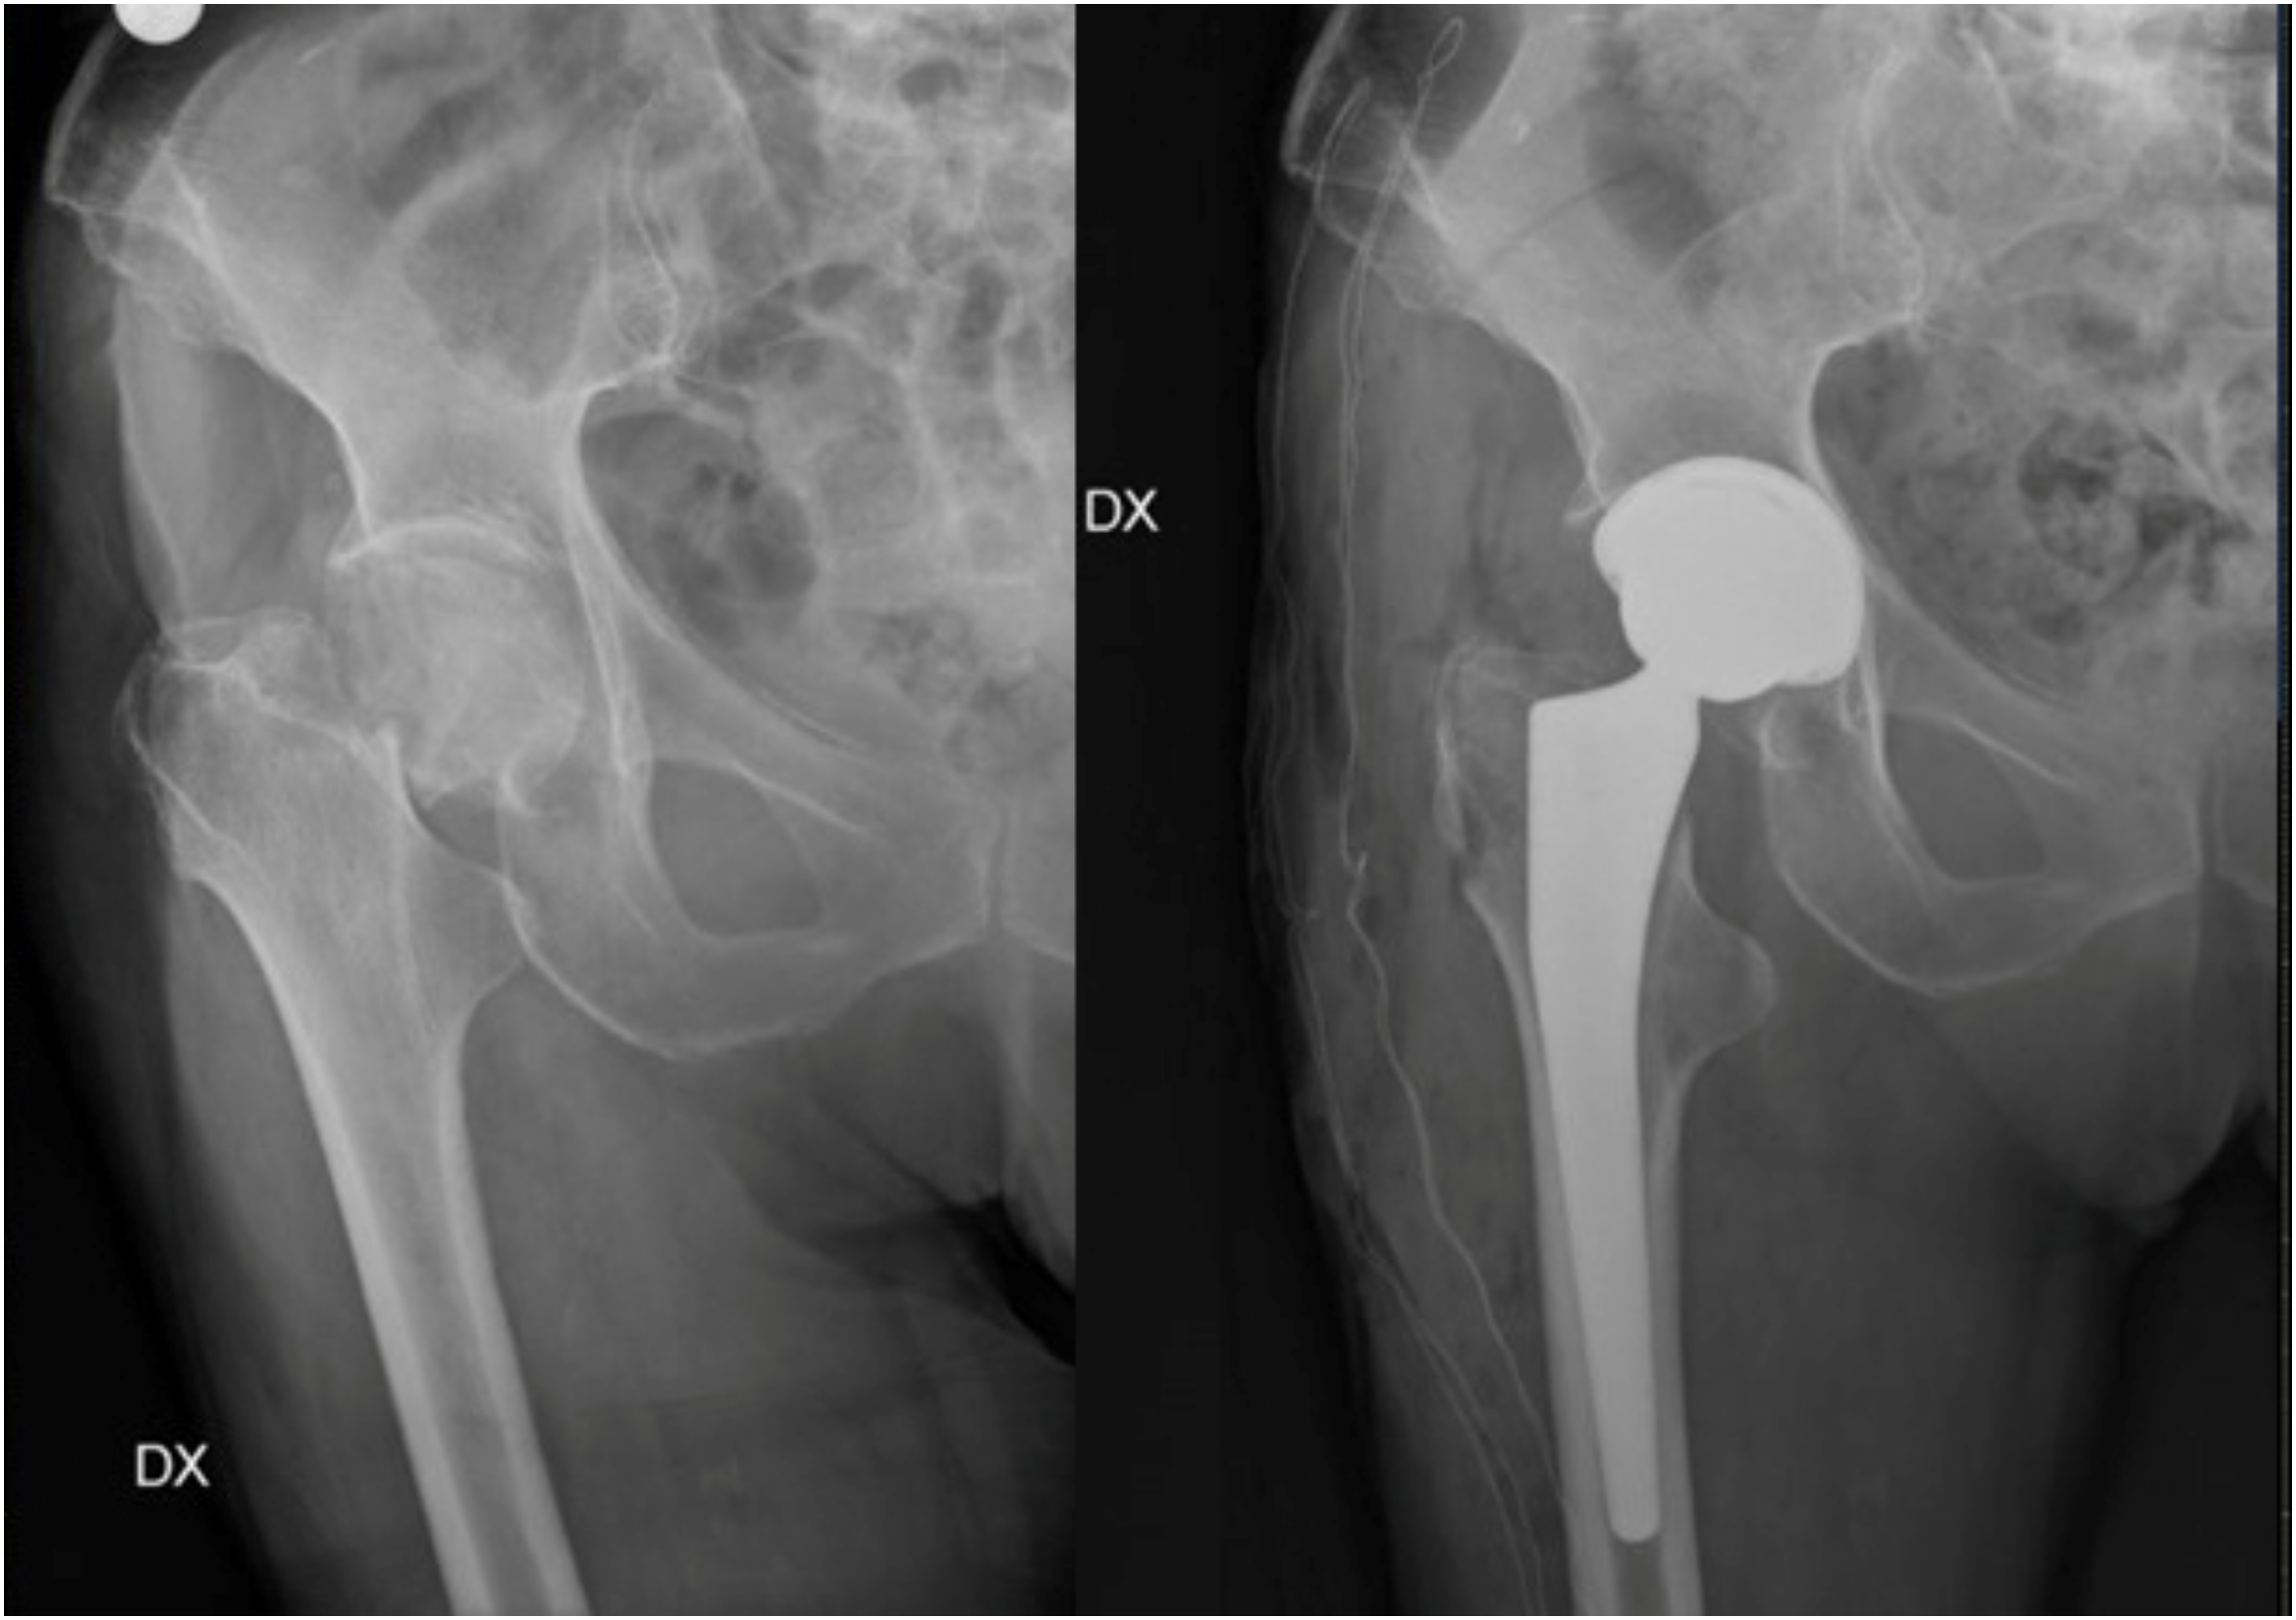

5. Surgical Management